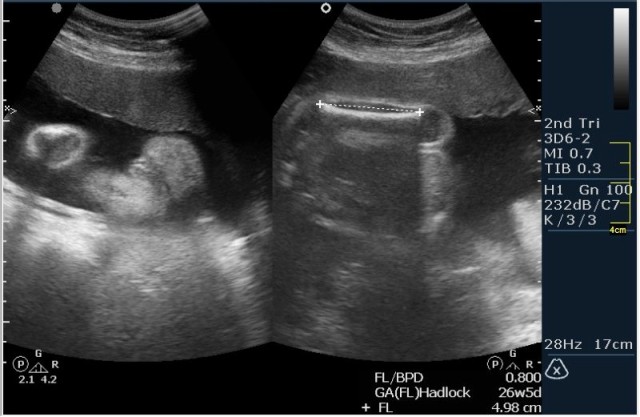

Женщина 23 года; из глухой деревни. К врачу обращалась один раз, когда забеременела. Дату последних месячных не помнит. Gravida 2, para 0. Направлена гинекологом для определения точного срока беременности и состояния плода.

1.Вентрикуломегалия/гидроцефалия (на сонограмме №1 размер задних рогов боковых желудочков 16мм при норме до 10 мм включительно;

На сонограммах головы плода визуализаируется гифдроцефалия, патогенетически связанная со спинномозговой грыжей (менингомиелоцеле) представленная в 2D и 3D режимах. В режиме Skeleton не удалось получить "картинку презентационного качества", плод начал сильно вертется; но рекоммендация очень грамотная :idea: , спасибо за ваш пост!